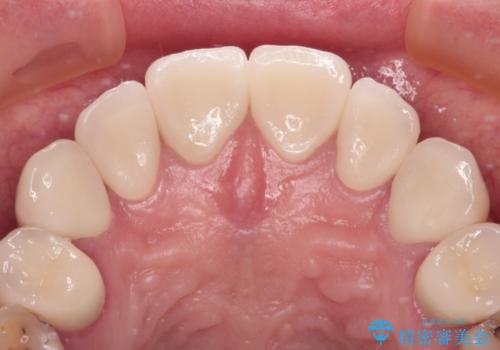

上顎前歯は歯肉退縮により歯根が露出していたため、事前に歯肉移植術により根面被覆を行い、その後にオールセラミッククラウンを装着することとしました。

歯肉移植術による根面被覆を行うかどうかは非常に悩まれていましたが、歯肉が覆われたことで長く見えていた歯の長さが整い、きれいな前歯の仕上がりとなりました。